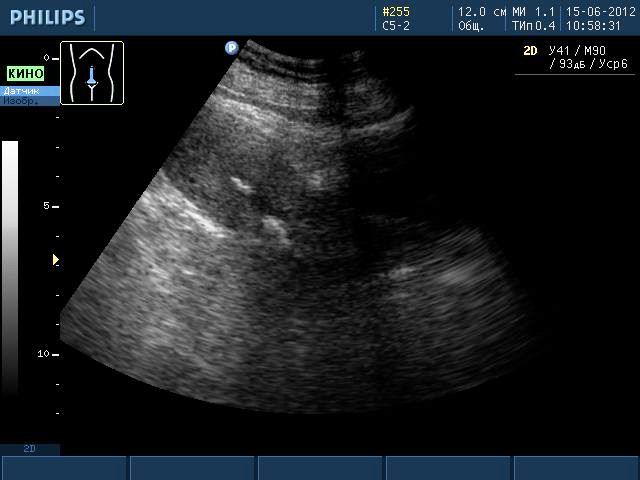

Такие образования хорошо видны при ультразвуковом исследовании, МРТ. Но во время УЗИ не видны ткани, из которых состоит образование, поэтому о наличии кальцината можно только предположить. Такая ситуация требует дополнительного обследования женщины, чтобы исключить заболевания гораздо серьезнее, чем наличие отложений солей кальция.

Кальцинат на УЗИ